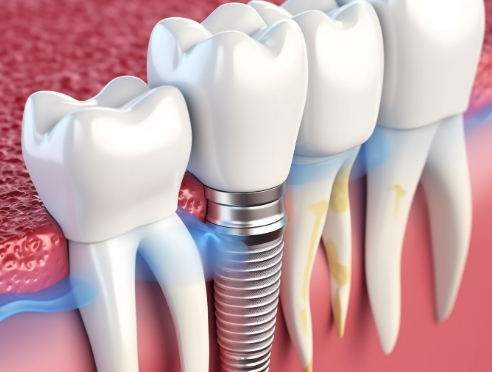

임플란트는 정확한 진단과 계획을 기반으로

여러 단계를 거쳐 진행되는 치료입니다.

환자분의 구강 상태에 맞춰

단계별로 안전하게 진행됩니다.

뼈 상태·신경 위치 등을 고려해

식립 위치와 시술 계획을 세웁니다.

계획된 가이드에 따라 안정적으로

임플란트를 식립합니다.